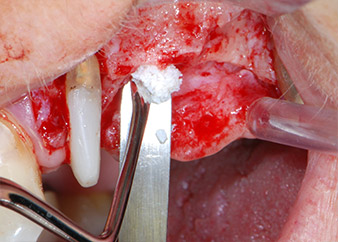

Antes de la colocación del implante y tras la verificación de que la membrana de Schneider estaba intacta (figura 9), la base interna del seno se aumentó en las dos posiciones del implante con un material sustituto de hueso xenógeno (Bio-Oss, Geistlich Biomaterials) (figura 10).

posición 26, la integridad de la membrana del seno se comprobó con una sonda periodontal CPITN con punta esférica.